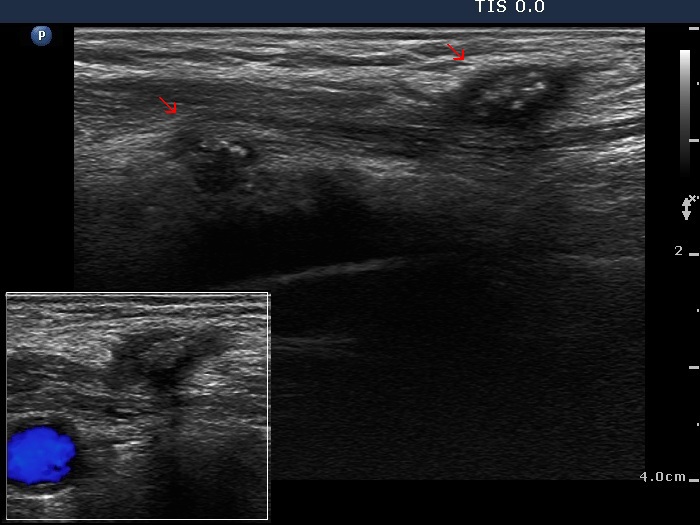

Granulation around surgical thread (cytological diagnosis) - case 1475

There are two granulations both in the left, horizontal and in the right, longitudinal images (arrows). The shape of the masses is irregular. The granulations are hypoechogenic and have one or more echonormal foci.